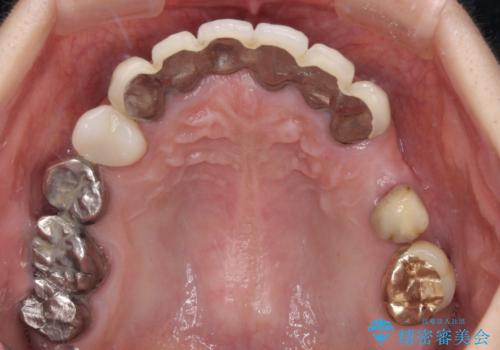

- 以前通院していた医院で、奥歯のインプラント埋入、前歯部のインビザライン矯正を行ったものの、そのまま放置してしまったとのことで来院された患者様です。

下顎前歯や上顎奥歯などをワイヤー装置により部分矯正を行い、歯列を整えた上でインプラン部分を含めてオールセラミッククラウンにて補綴治療を行うこととしました。

インプラント上の仮歯がボロボロになり、前歯に非常に負担のかかる状態であったため、早急に奥歯の仮歯を修復し、矯正治療、奥歯の補綴治療、前歯の補綴治療と順々に進めて行きました。